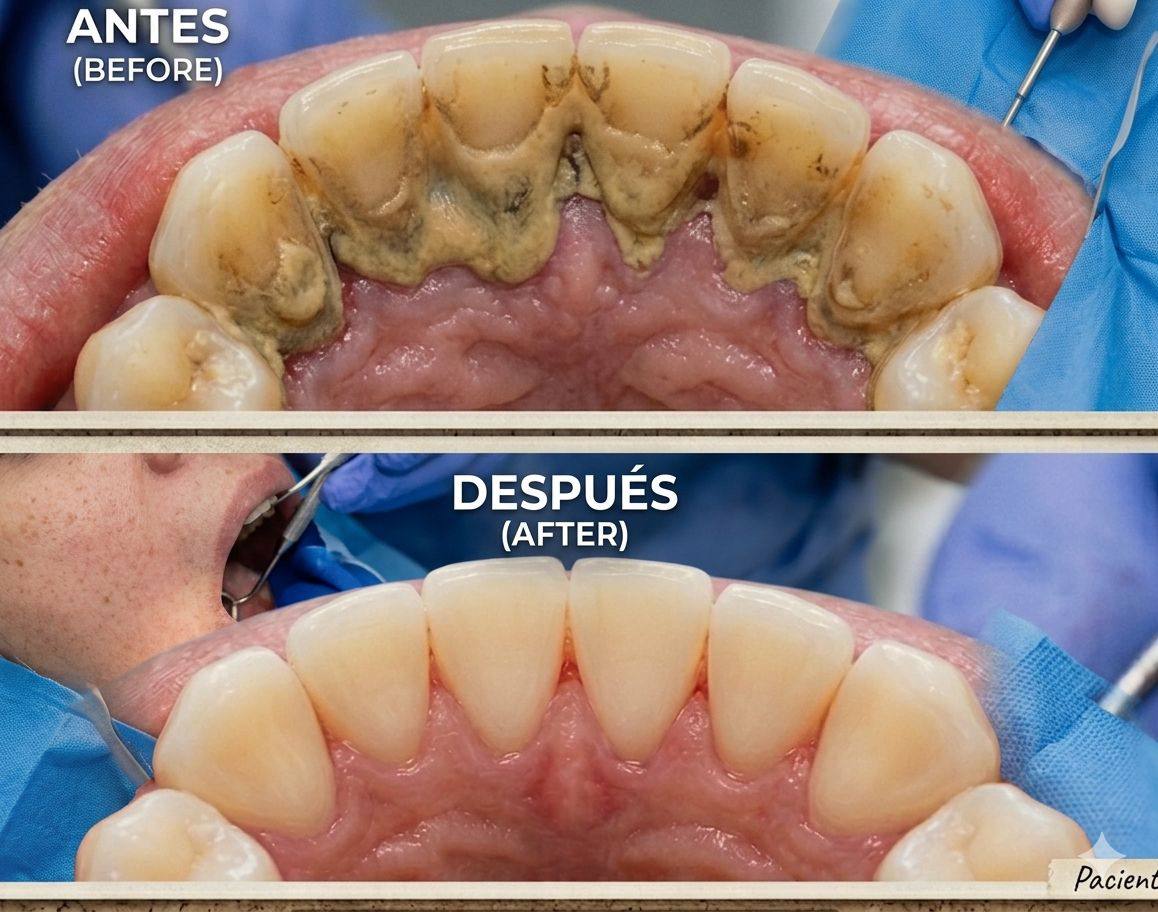

Periodoncia

Cuidamos la salud de tus encías y tejidos de soporte dental. Tratamos enfermedades como gingivitis y periodontitis para prevenir la pérdida de dientes y mantener una sonrisa sana a largo plazo.